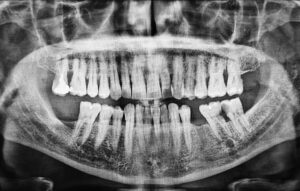

If you are considering dental implants, you may have been told that you need to take CBCT scans or dental X-rays before the procedure. It is not uncommon for patients